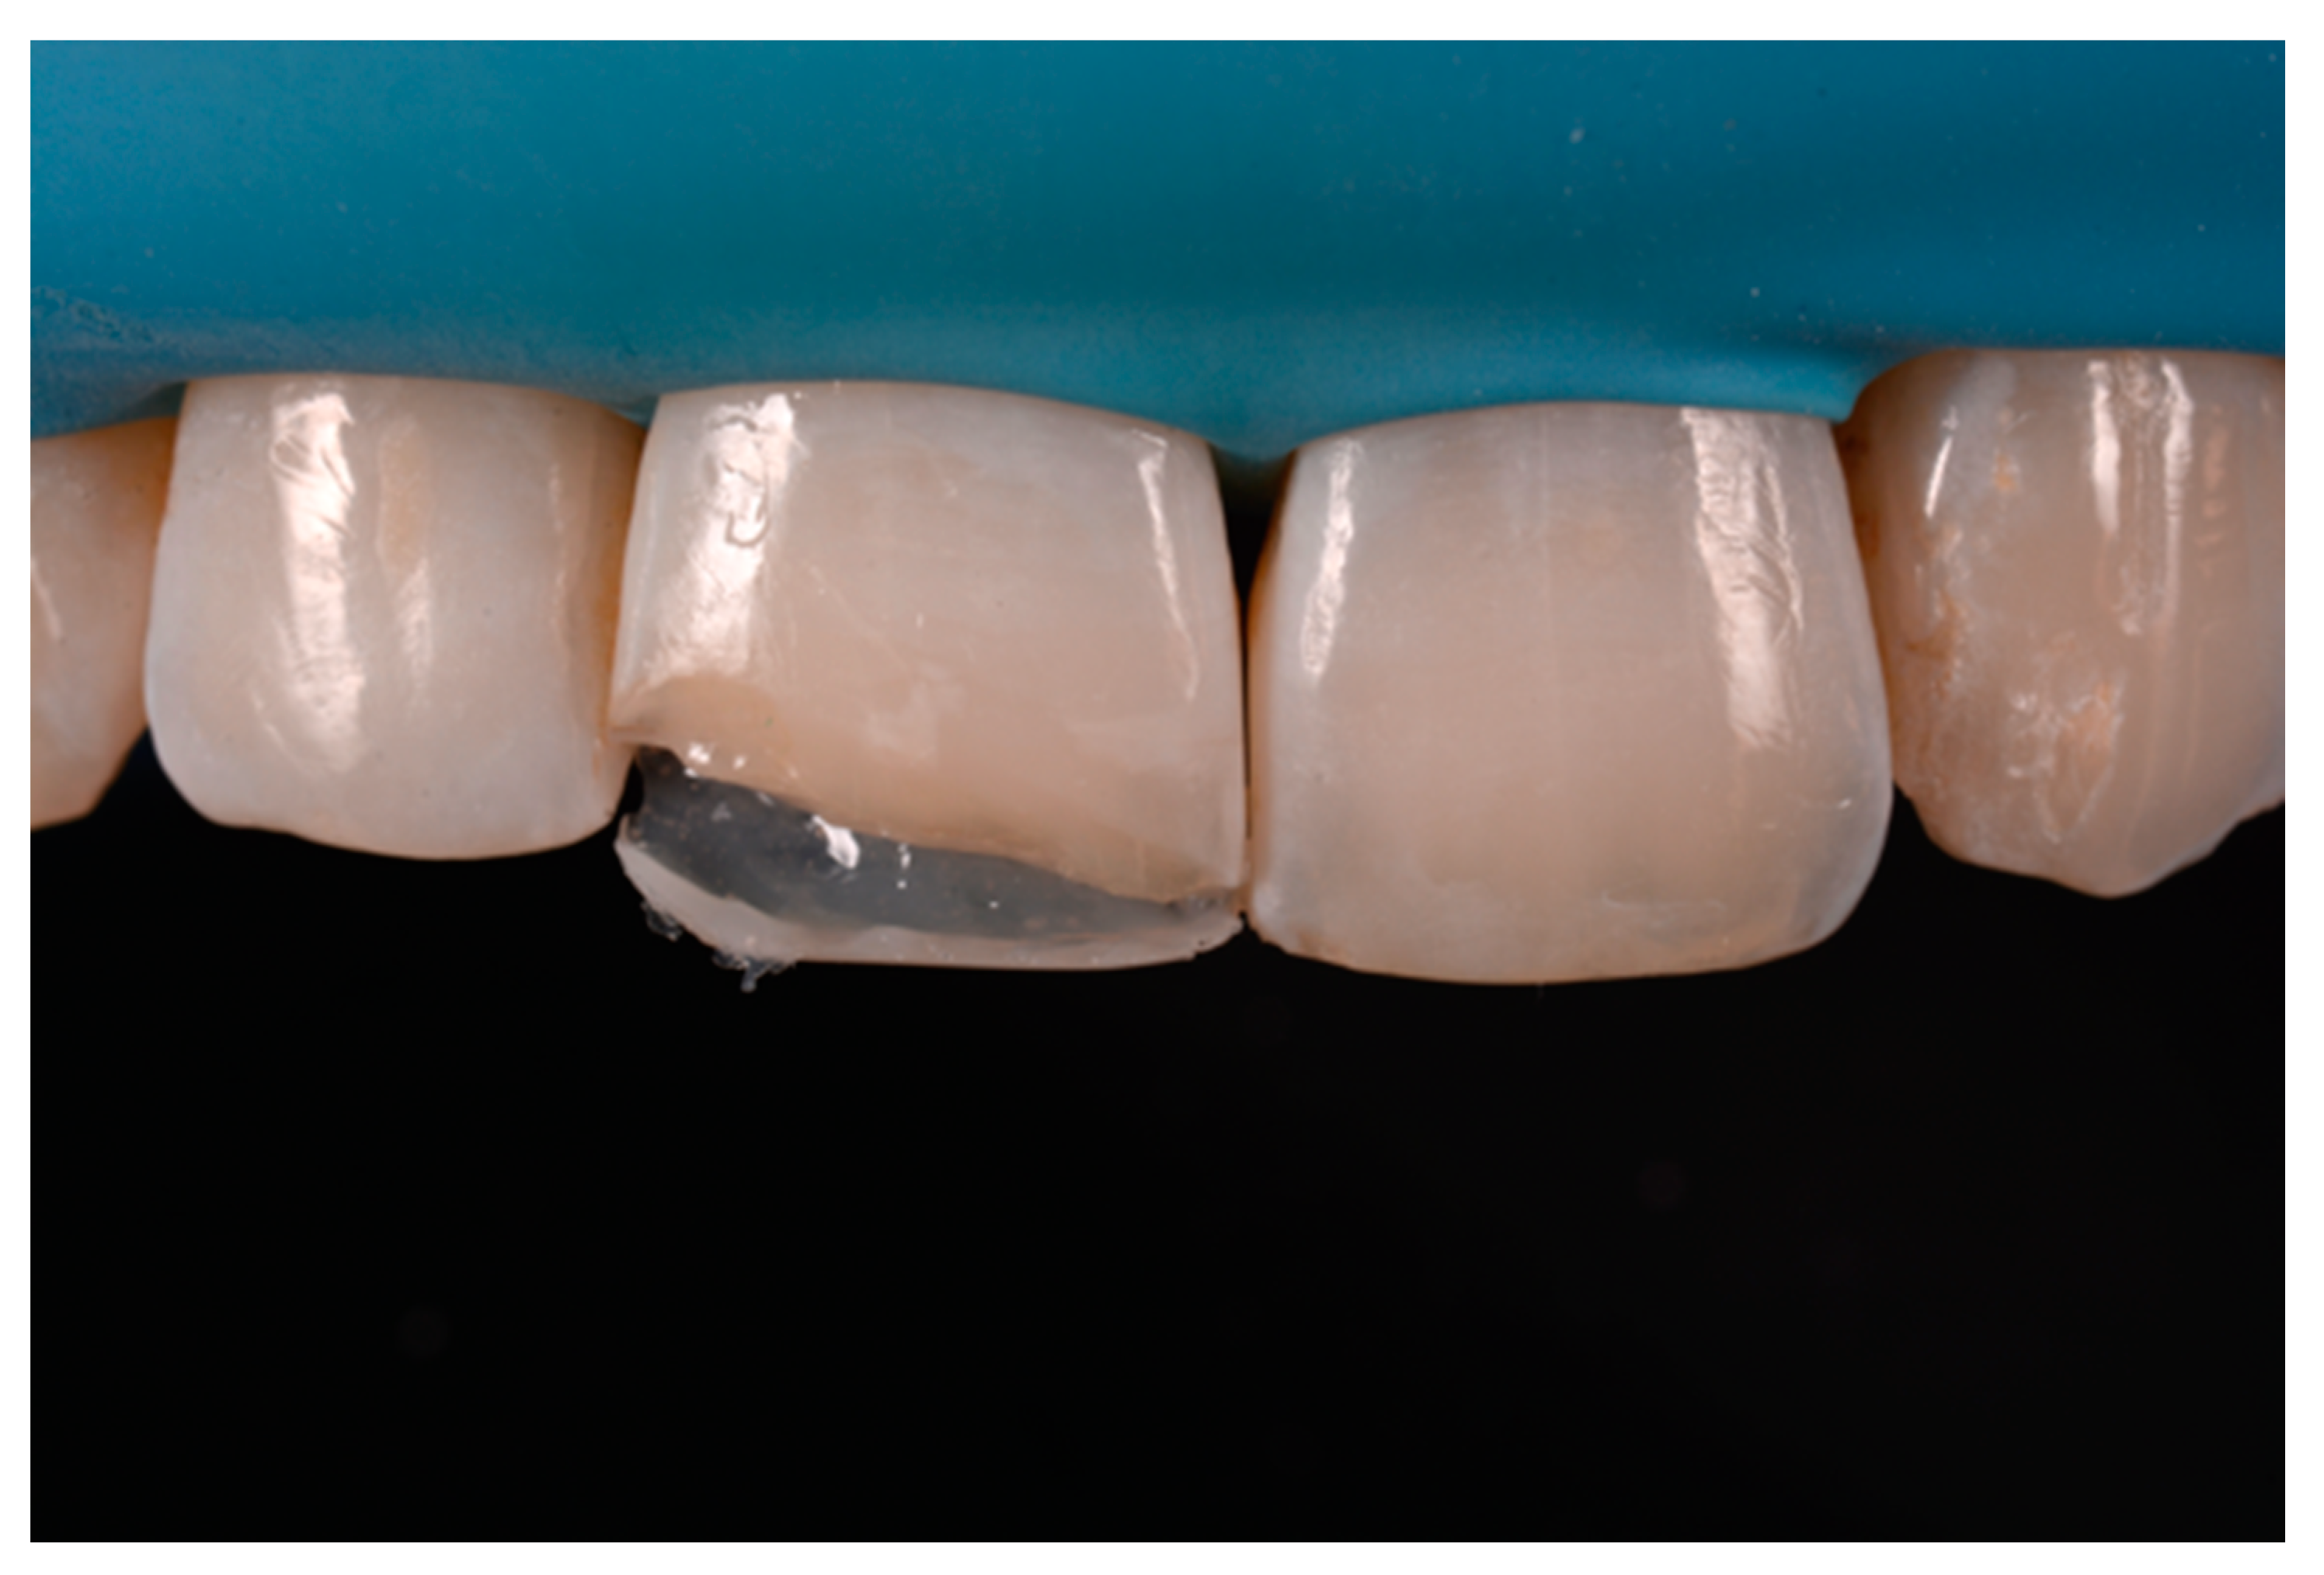

Once completed, the two frames (Clearfil Majesty ES-2, A1E, A2D, Kuraray Noritake Dental, Tokyo, Japan) showed internal and external excesses that were reduced using diamond burs and discs (Figure 33 and Figure 34) strictly following the procedure described in Section 2.1.2 of present article. Excesses were removed from the distal-incisal angle of #2.1 allowing therefore to obtain the desired translucency. After silane application and bonding procedure (Figure 35) as described in Section 2.1.2, restorations were completed (Figure 36 and Figure 37). They both show satisfactory clinical integration 1.5 years post-operative (Figure 38 and Figure 39).

Figure 33.

Frame imprecisions are corrected by reducing interproximal wall from the internal side. Reprinted from Restauri diretti nei settori anteriori, G. Paolone, S. Scolavino, © 2021, with permission from Quintessence Publishing Italy.

Figure 34.

Frame is also trimmed reducing external outline. Reprinted from Restauri diretti nei settori anteriori, G. Paolone, S. Scolavino, © 2021, with permission from Quintessence Publishing Italy.